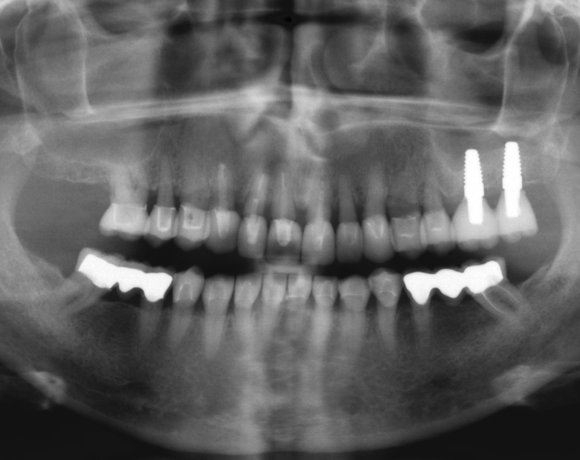

Beim Internen Sinuslift wird durch die Implantatbohrung ohne die Schleimhaut des Kieferhöhlenbodens zu durchbrechen Knochenmaterial unter die Schleimhaut geschoben, um neues Knochenwachstum, um das in die Kieferhöhle eingeschraubte Implantat, zu bekommen.

Der vorliegende Patientenfall zeigt eine komplette Neuversorgung der vorhandenen Metallkeramikkronen mit vollkeramischen Restaurationen. Zusätzlich wurde im Oberkiefer die Zahnreihe mit zwei Implantaten, für die fehlenden Molaren, ergänzt. Da keine ausreichende Knochenhöhe vorhanden war wurde ein interner Sinuslift geplant.